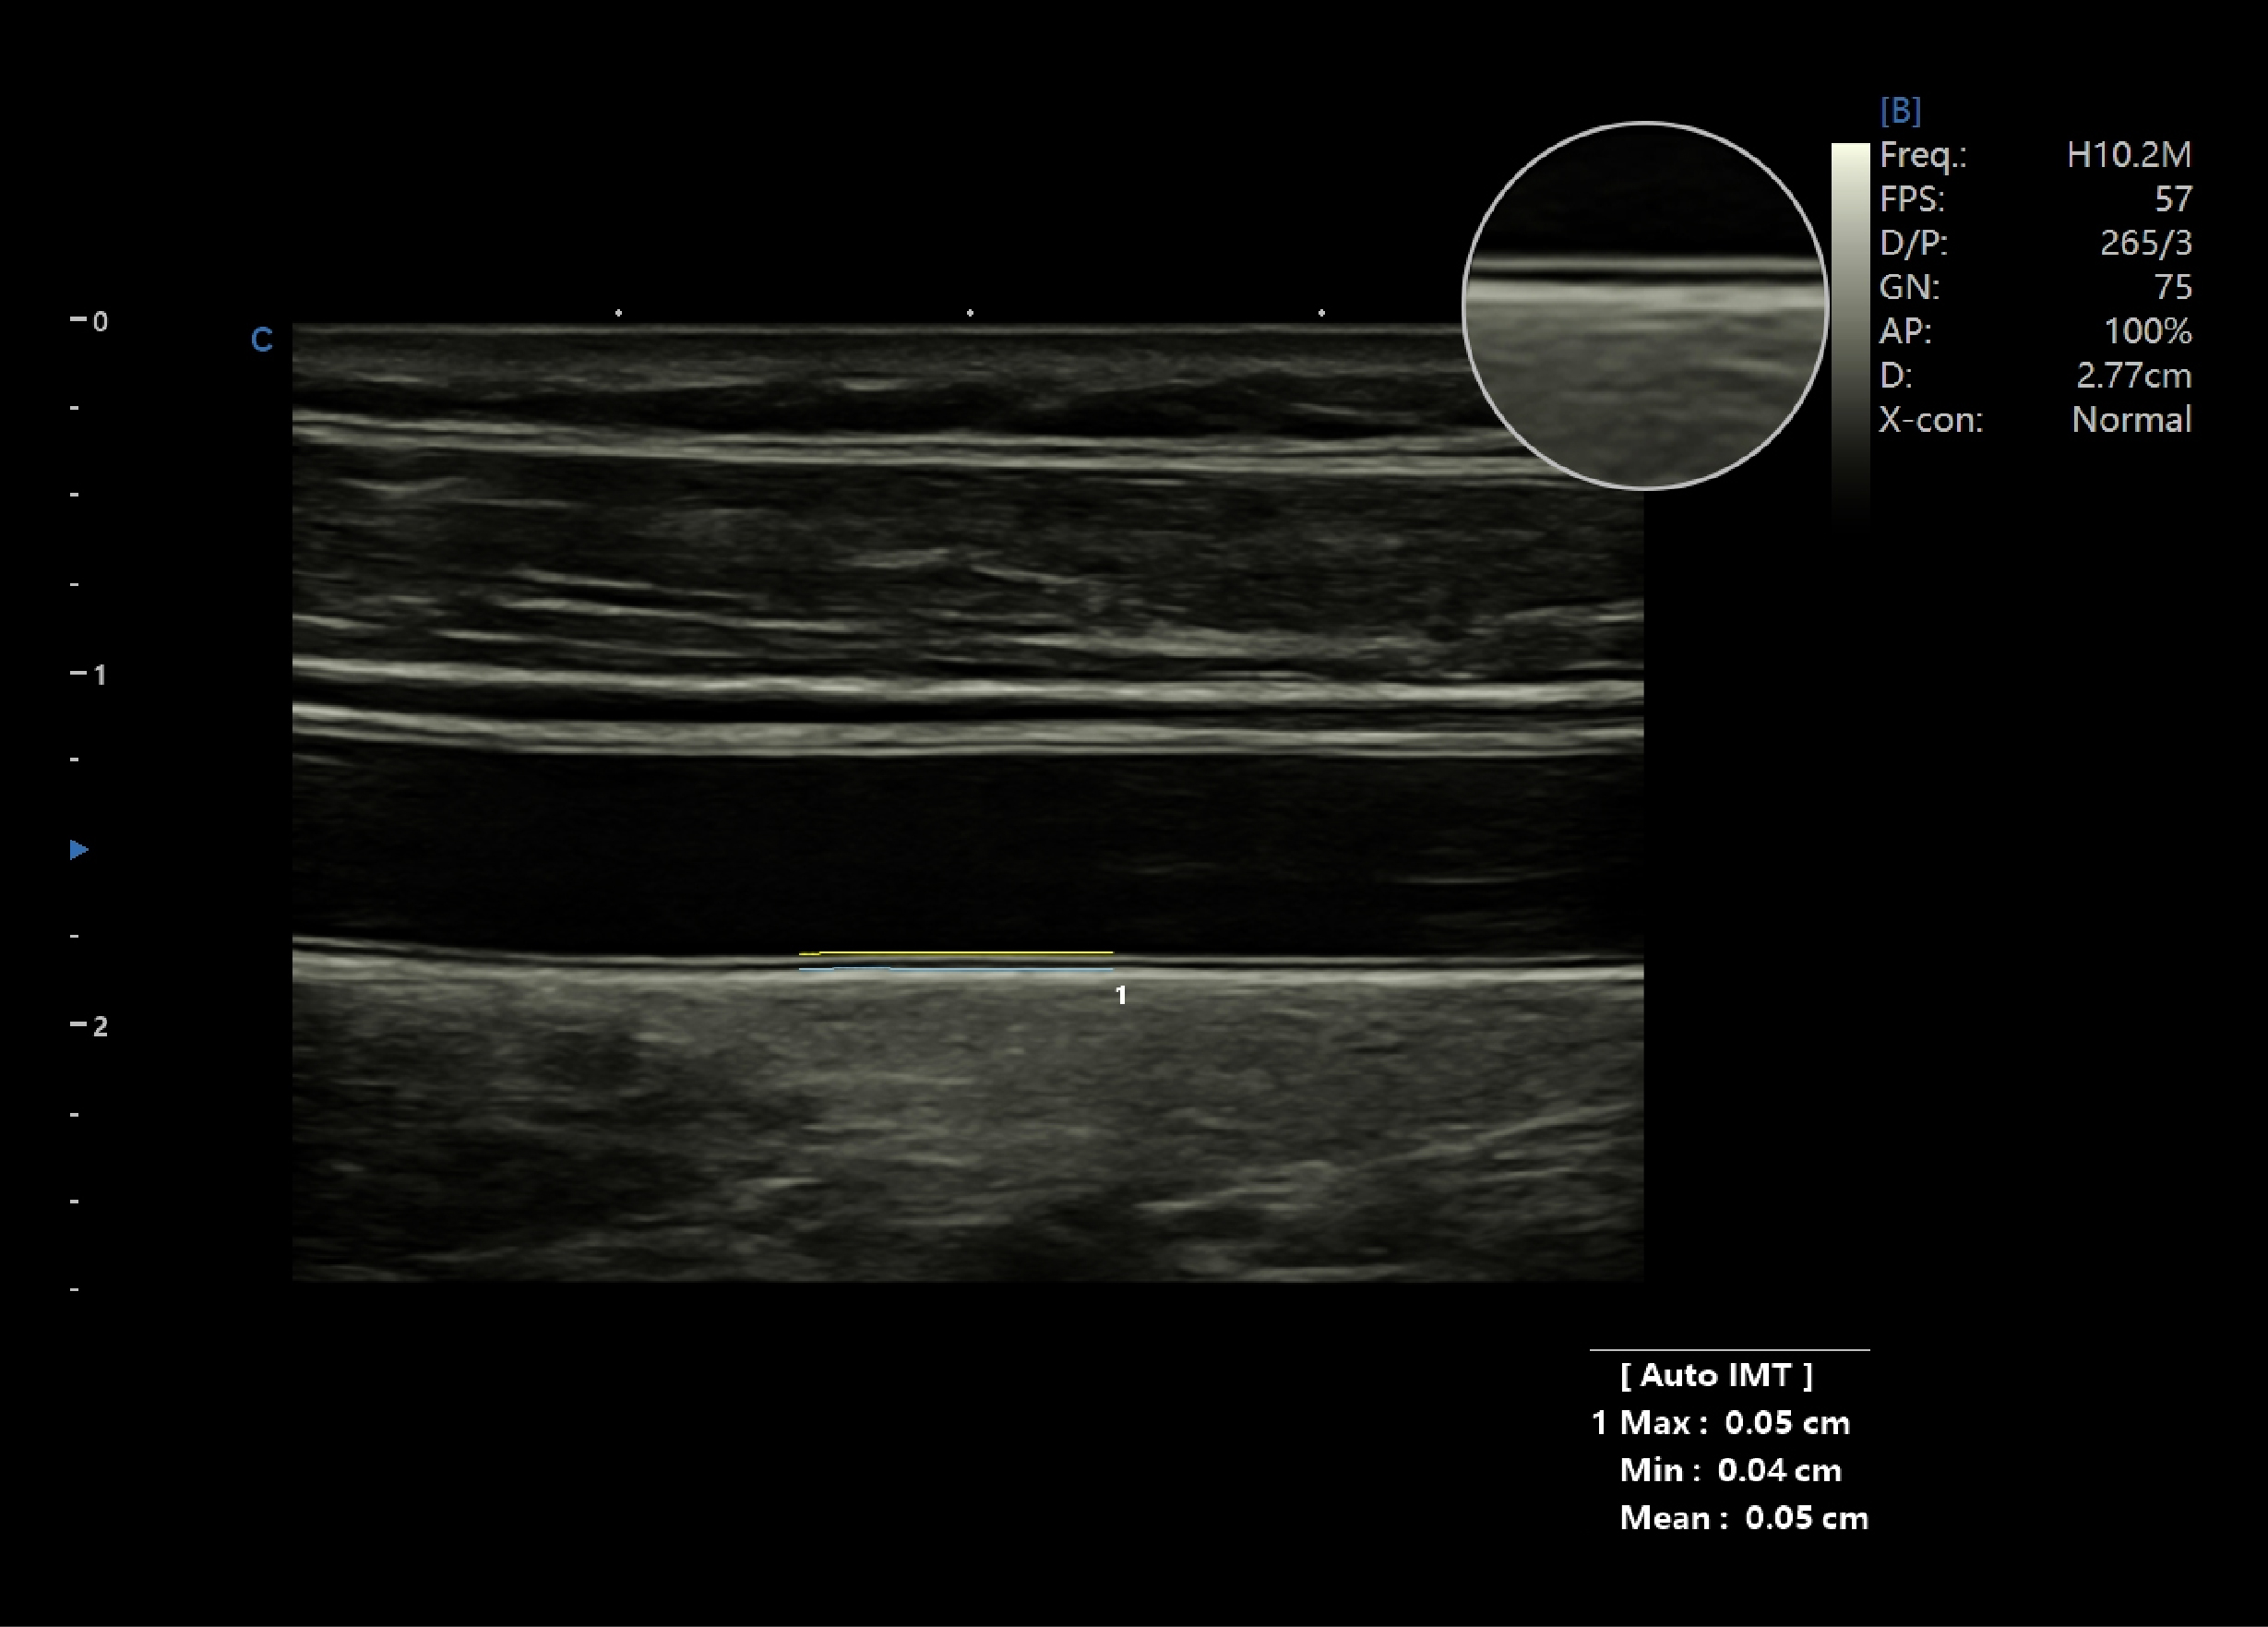

测量内膜厚度,在一个清晰的有内膜的B模式图像上,使用此功能,系统将会计算内膜的厚度并显示在屏幕上。